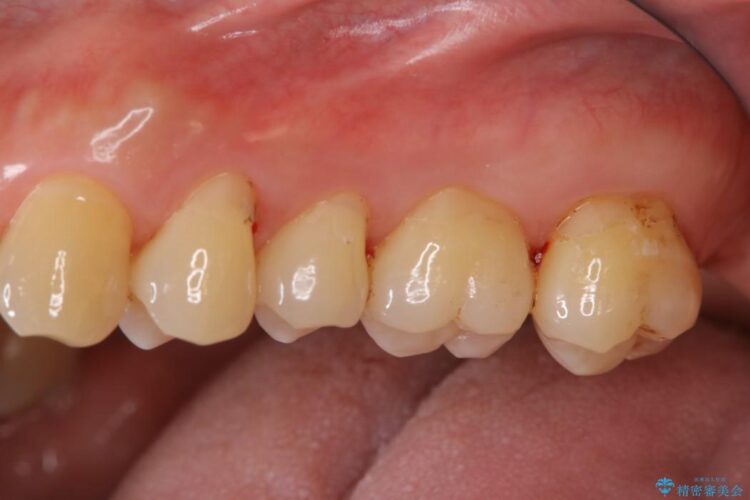

【40代男性】歯にこびりついた着色のクリーニング

普段からコーヒーをよく飲まれる方で、3年間歯医者に行かれておらず、定期健診も込みでご来院されました。

堅くこびりついていたステインも1時間コースのPMTC(プロフェッショナルクリーニング)できれいな状態になりました。